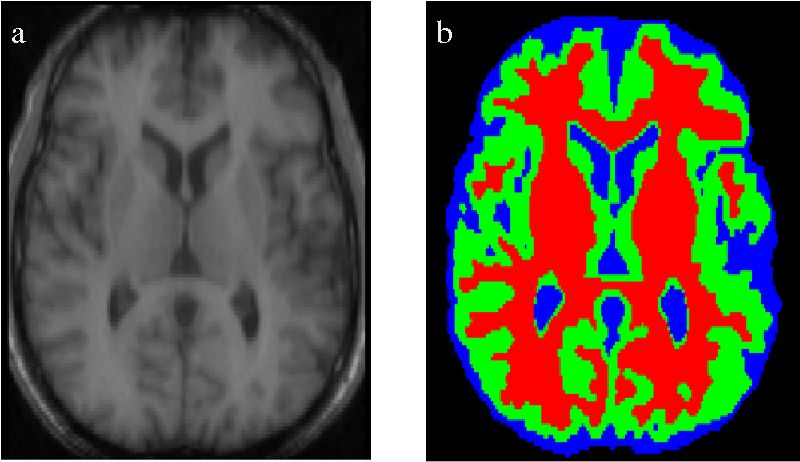

医学影像分割

语义分割技术也被用于在医学扫描影像中识别显著性元素。该方法对识别图像中的异常(如肿瘤)十分有效。提升算法的准确率并解决低召回率的问题对于这种应用十分重要。

医学扫描影像的分割

我们还可以将一些不那么关键的操作自动化处理,比如根据语义分割后的 3D 扫描影像估计器官的体积。